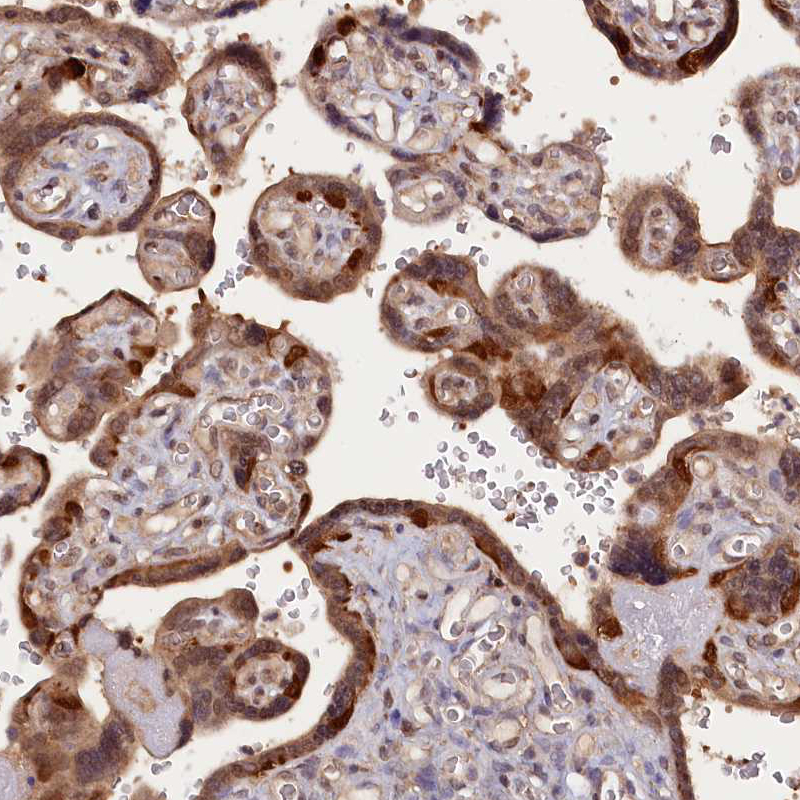

Immunohistochemical staining of human Fallopian tube shows strong cytoplasmic positivity in glandular cells.